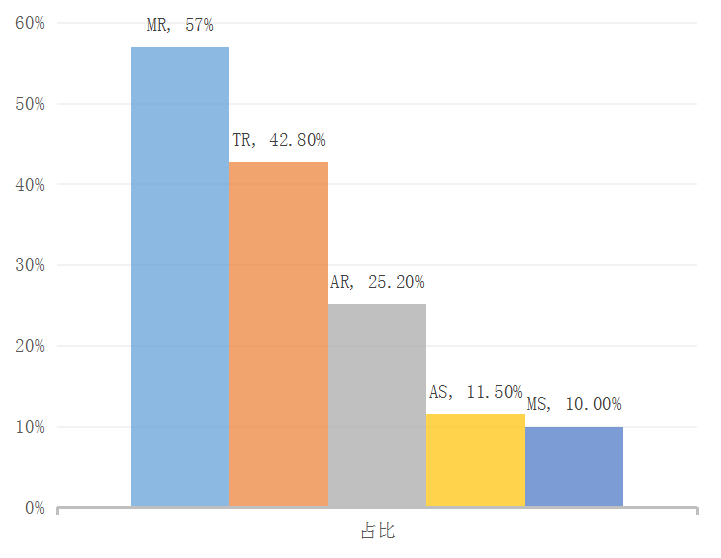

二尖瓣关闭不全(Mitral Regurgitation,MR)是一种常见心脏瓣膜病,其发病率随年龄增长呈逐渐增加趋势,并伴有较高的再住院率和死亡率。在中国老年瓣膜性心脏病住院患者队列研究数据中发现,MR在心脏瓣膜病比重较大,介入治疗亟需发展。长期以来,外科手术是治疗MR的唯一标准。近年来,TEER逐渐发展成熟,成为MR手术的一种替代方案。然而,由于二尖瓣反流从操作、器械、病人评估等方面存在一定的难度,二尖瓣修复技术开展的数目比经导管主动脉瓣置换术要低得多。

二尖瓣反流(MR)——未被满足的临床需求

中国老年瓣膜性心脏病住院患者队列研究(China-DVD)2018公布数据